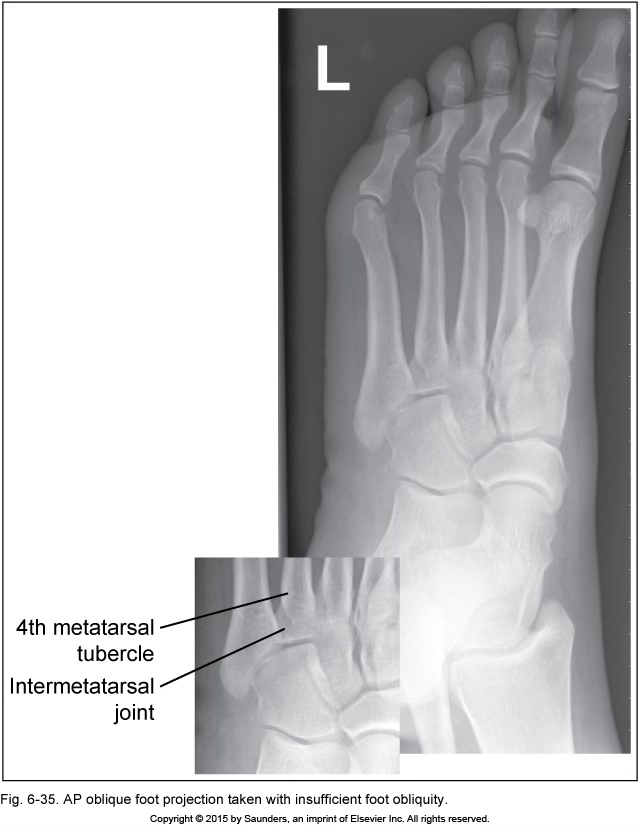

AP oblique foot

insufficient foot obliquity